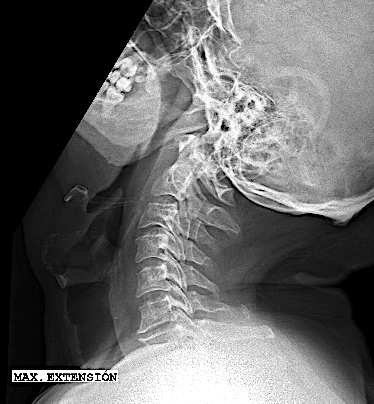

- a las peculiaridades anatómicas de la región: el mediastino anterior con los grandes vasos dificulta el acceso a la columna (inclusive a cirujanos torácicos y cirujanos vasculares). El abordaje clásico cervical puede requerir en los niveles más altos (Th1 y Th2) una esternotomía con osteotomía de clavícula y reconstrucción posterior. Generalmente, el cálculo del ángulo Thoracic Inlet Angle (TIA) puede predecir si será un abordaje más o menos dificultoso (para discos cervicales bajos o Th1-Th2 con TIA >60º). En estos casos, suelo informar al paciente la posibilidad de esternotomía (o completar con abordaje posterior la resección) y para el día de la intervención solicito la colaboración de un cirujano torácico. El abordaje posterior es mucho más sencillo, sin embargo plantea como principal dificultad técnica la imposibilidad de descomprimir el canal central en su sector anterior. Otro inconveniente a tener en cuenta en la elección de la vía posterior es la potencial secuela de cifosis secundaria a la resección de elementos de estabilidad posteriores (músculos, ligamentos, huesos), probable causa de dolor cervicotorácico mecánico.

Por las razones expuestas, a pesar de un thoracic inlet angle bastante alto, opté por realizar un abordaje anterior con descompresión + artrodesis IS con cajas atornilladas C7-Th1.